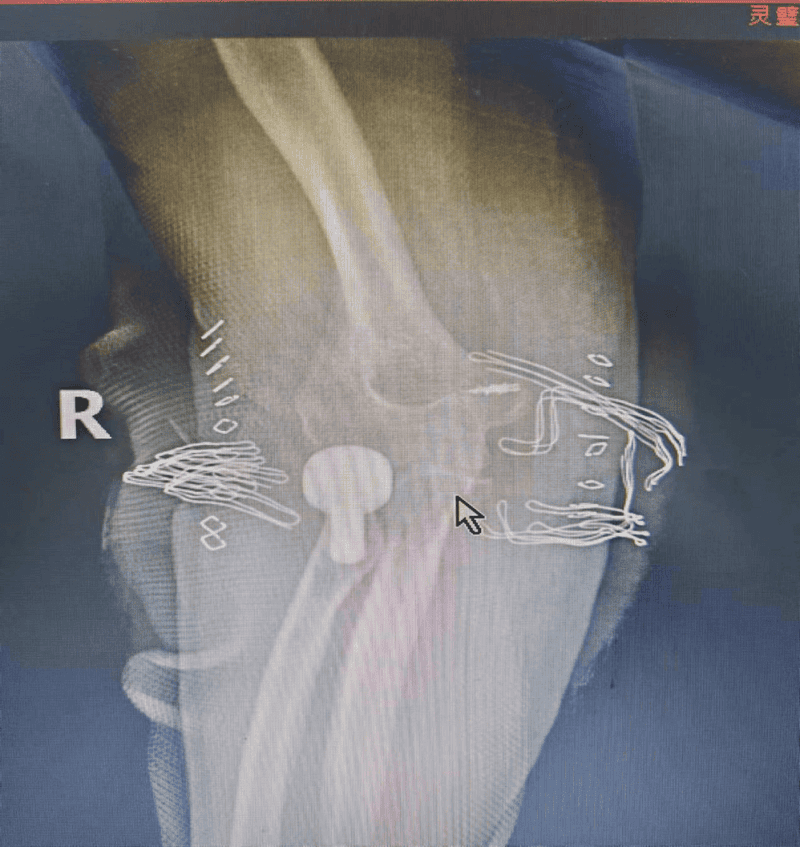

安徽省第二人民医院灵璧医院喻德富副院长、骨科博士、主任医师指导手术。术中探查发现胡女士桡骨头粉碎性骨折,骨碎片游离,尺侧副韧带、环状韧带断裂。骨科手术团队密切协作,按照规范手术治疗方案,小心取出碎骨块,放入假体稳定复位,锚钉重建尺侧受损韧带。术后石膏固定,消肿,预防感染,指导康复锻炼等治疗。

图为术中透视